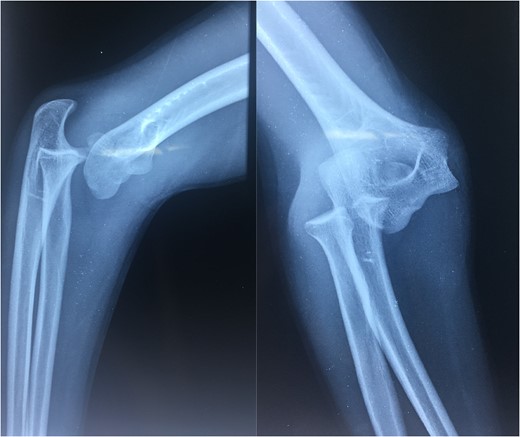

A 14-year-old male patient presented to the emergencies department complaining of intense pain in the left elbow secondary to a fall with an outstretched hand while practicing soccer. He had no significant comorbidities. At physical examination he presented with deformity located on the left elbow, he was unable to passively or actively mobilize it, he reported paresthesias and diminished sensation located on the fifth and fourth digit. X-rays showed a dislocation on the left elbow and an avulsive fracture of the medial epicondyle of the distal humerus (Fig. 1). He was taken to the operating room where a closed manipulation was performed; however the reduction was not achieved due to the interposition of the fractured medial epicondyle. A medial approach to the elbow was performed; intra-operative findings included rupture of the medial capsule and intra-articular interposition of the fragment of the medial epicondyle with a posterolateral dislocation of the elbow, the ulnar nerve showed compressive injuries at the site of the fracture (Fig. 2). Extraction and fixation of the interposed intra-articular fragment was performed followed by elbow reduction and a medial capsule repair, without ulnar nerve transposition (Fig. 3). The patient was left with a posterior splint for a month. After a 3 month follow-up, he has recovered full range of motion of the elbow with recovery of strength and sensation over the distribution of the ulnar nerve.

X-rays showing the result of the first attempt of closed manipulation and open reduction.